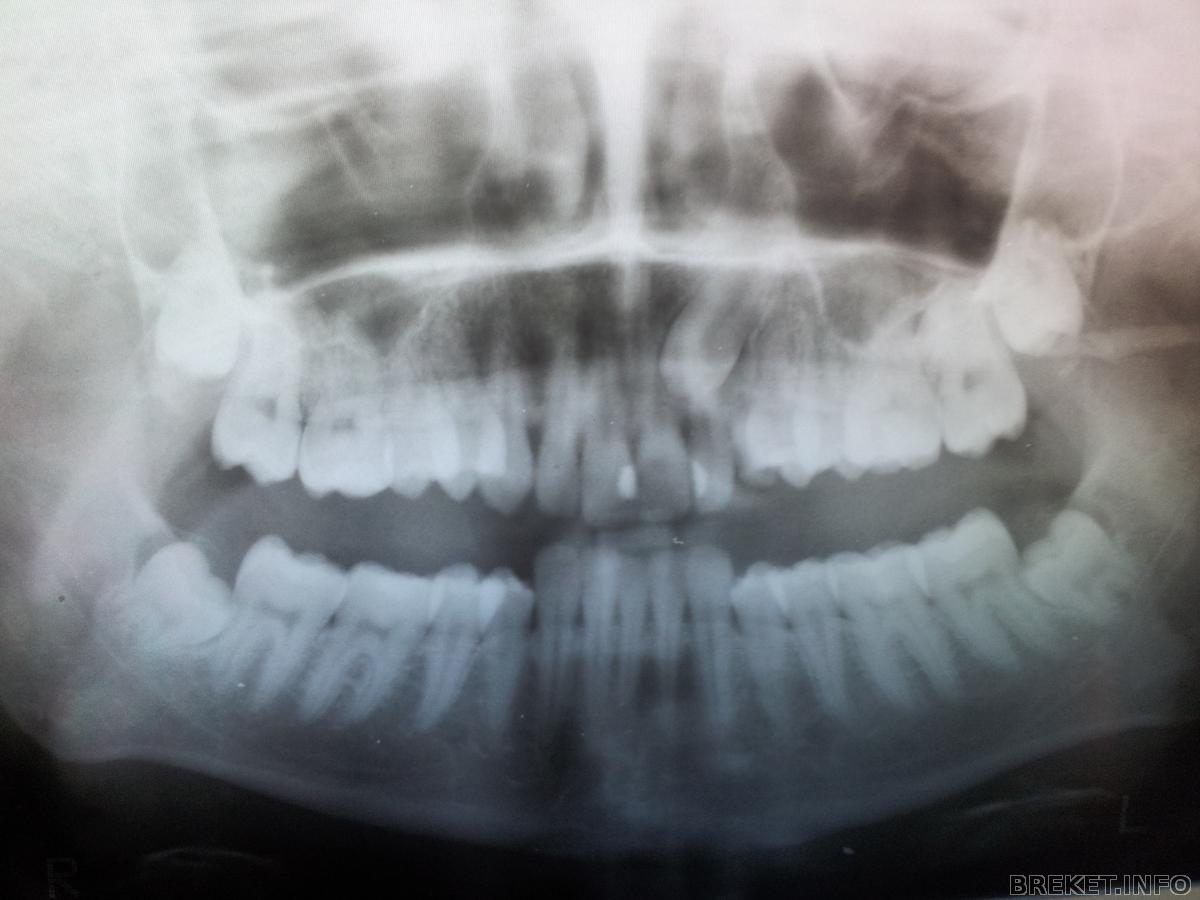

Снимки

Снимки моего клыка.

Да, лежит он очень высоко, но зато хорошо лежит)